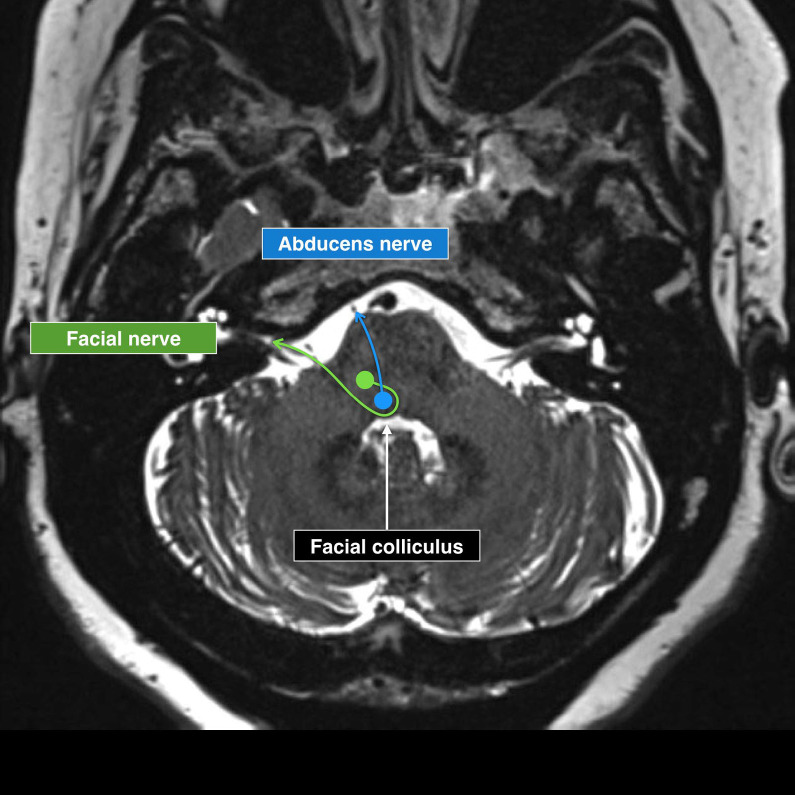

面肌痉挛(HFS)是整形外科医生需要了解的一个重要情况,因为它会显著影响患者的生活质量,并使美容和重建手术复杂化。磁共振成像(MRI)在诊断HFS、评估神经血管关系和计划治疗方面变得至关重要。MRI横断面扫描常显示面神经附着点下桥向上移位,提示HFS的神经血管受压(NVC)。对于神经外科医生来说,重要的解剖学特征包括小脑萎缩和“小后窝”,这可以通过缩小液体空间导致HFS。HFS患者的后窝通常更充血,解剖平面可能加剧椎基底动脉外侧偏曲。此外,评估乙状窦优势和其他解剖变异对手术计划至关重要,特别是在动脉高压可能影响髓质压迫的情况下。

Hemifacial spasm (HFS) is an important condition for plastic surgeons to understand, as it significantly affects patients' quality of life and can complicate aesthetic and reconstructive procedures. Magnetic resonance imaging (MRI) has become vital in diagnosing HFS, assessing neurovascular relationships, and planning treatment. Transverse MRI scans often show an upward displacement of the inferior pons at the facial nerve attachment point, signaling neurovascular compression (NVC) in HFS. Important anatomical features for neurosurgeons include cerebellar atrophy and a "small posterior fossa," which can lead to HFS by narrowing fluid spaces. The posterior fossa is often more congested in HFS patients, and anatomical flatness may exacerbate lateral deviation of the vertebrobasilar arteries. Additionally, evaluating sigmoid sinus dominance and other anatomical variations is crucial for surgical planning, particularly in cases of arterial hypertension that may affect medullary compression.